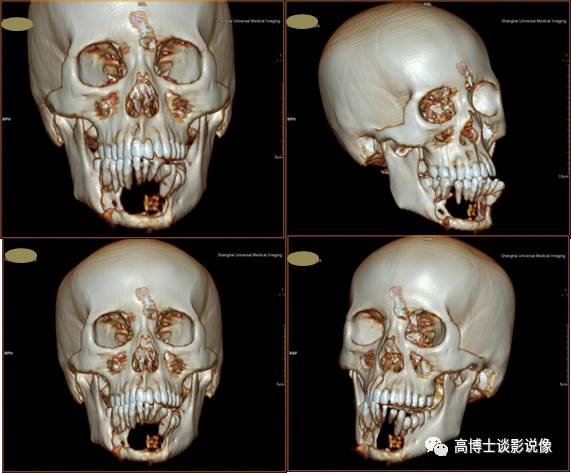

二、下颌骨肿瘤CT三维骨重建

全容积VRT重建可观察肿瘤全貌,了解颌骨来源肿瘤部位、形态、大小;了解骨质破坏的类型、性质、程度、边界及骨膜反应等情况;了解肿瘤与周围结构如牙齿、下颌骨、牙槽骨、软组织、大血管间关系;了解有无异常供血动脉,为颌骨肿瘤的定位、定性诊断及选择治疗方案等提供依据。

以上两个作品对于不学医的朋友来说相当恐怖吧,通过计算机后处理技术把头部软组织去除后,剩下的头骨就是俗称的“骷髅头”了,医生们就是根据上面的CT重建信息来观察解剖结构和病灶及其周围情况的。